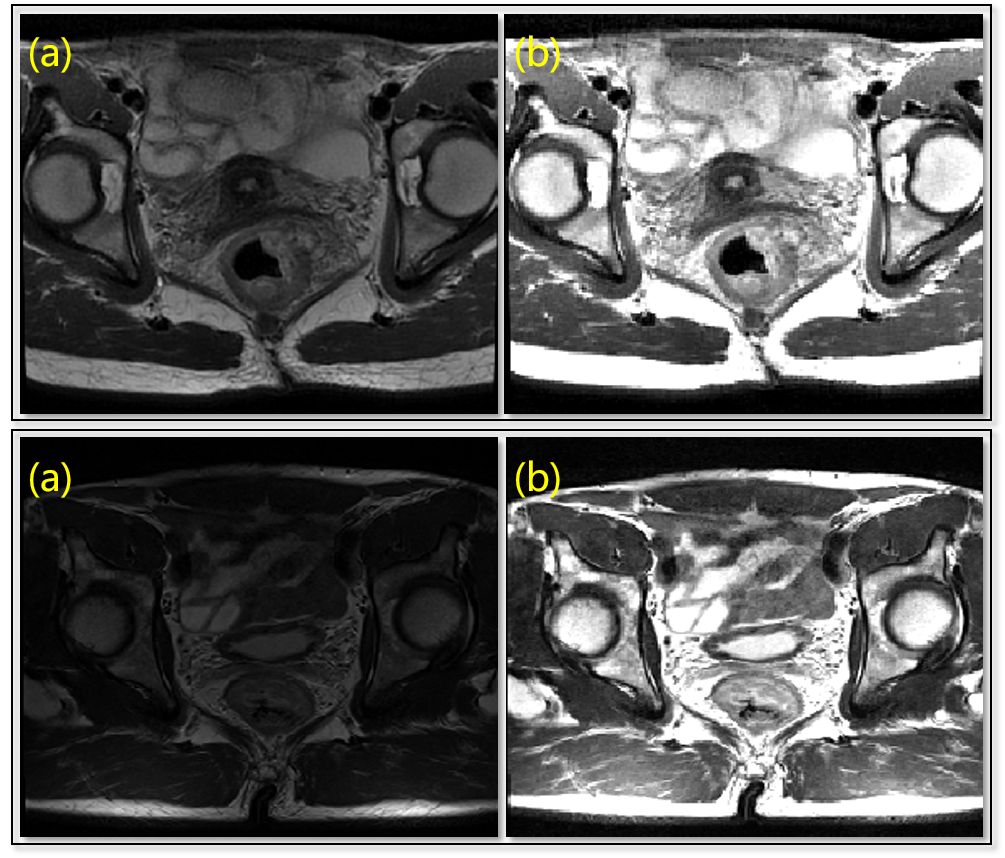

Refer to caption

Figure 4: Examples of: (a) Original Images (b) Normalized Images. The intensity of homogeneous tissues from images acquired under different imaging configurations are normalized to identical ranges.

Different spacing rates are normalized to 4.0×1.0×1.04.01.01.0{{4.0}\times{1.0}\times{1.0}} as the HighRes set. Some part-based methods listed in TABLE 2 employ down-sampled image sets, namely LowRes set of 4.0×2.0×2.04.02.02.0{{4.0}\times{2.0}\times{2.0}} mm spacing and MidRes set of 4.0×1.5×1.54.01.51.5{{4.0}\times{1.5}\times{1.5}} spacing. To normalize the intensities of input images acquired under different imaging configurations and field of views, we perform in-body intensity normalization to exclude the affect of inconsistent body-to-background ratios. By OTSU[54] thresholding, connectivity analysis and closing operation, body masks are extracted as foreground and other voxels are set as background. The mean intensity and standard deviation are computed within the body mask according to following formulas:

A few examples of the comparison between original images and intensity-normalized images are illustrated in Fig. 4.